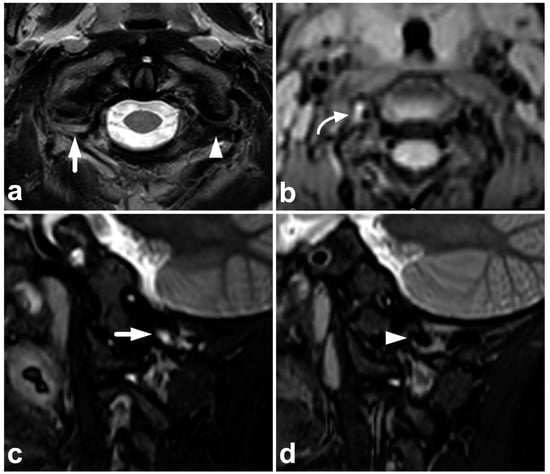

Figure 8.

(a) Axial T2-weighted. (b) Coronal PD-weighted. (c) Right-sided off-midline sagittal PD-weighted. (d) Sagittal PD-weighted. (e) Sagittal STIR. A 12-year-old male, football injury. The right alar ligament (white arrows) is torn. The right side of the transversal ligament is thickened and heterogenous, suggesting a partial distension injury (white arrowheads). The left alar ligament (black arrows) and the central and left-sided portions of the transversal ligament (black arrowheads) are intact. The tectorial membrane is unharmed (curved black arrows), but the apical ligament of the dens is poorly visible, probably torn (curved white arrow). Apparent asymmetry of the lateral atlantodental intervals is seen, but there are no signs of occipitocervical or atlantoaxial joint capsule disruption.